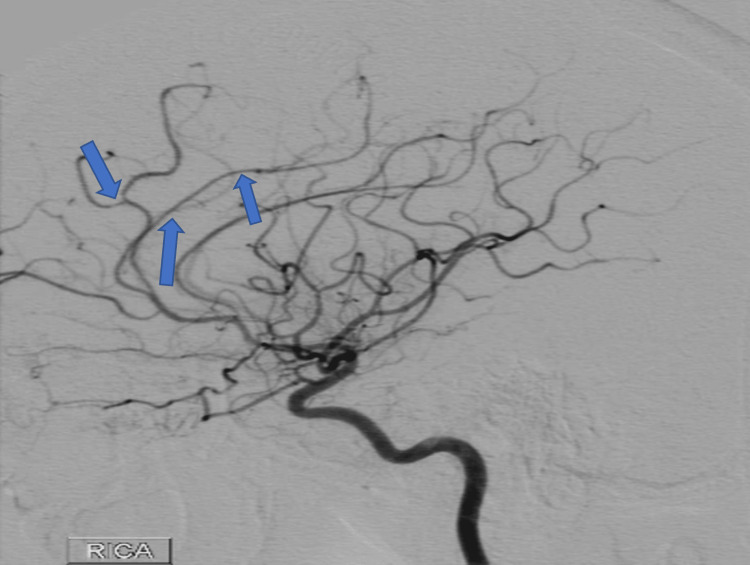

A year after her last outpatient appointment, she presented to the hospital with recurrent episodic thunderclap headaches with associated nausea, vomiting, and photosensitivity. Her neurologic examination was notable for aphasia without notable weakness. In the interim, she had established care with another neurologist who was closer to her home, who had discontinued verapamil and started the patient on venlafaxine for treatment of headaches and mood. CT Head without contrast revealed bilateral SAHs and a left frontal intraparenchymal hemorrhage, approximately 9.4 cc by ABC/2 formula (Figure 3). CTA Head and Neck with contrast again demonstrated multifocal stenosis of intracranial arteries. She underwent a second DSA, which demonstrated multifocal stenosis of intracranial arteries bilaterally (Figures 4–5). Angiogram found diffuse irregularities primarily affecting bilateral anterior cerebral arteries and, to a lesser extent, the bilateral middle cerebral and right superior cerebellar arteries. The patient also underwent brain biopsy with hematoma evacuation. Rheumatological workup was repeated and unremarkable. Lumbar puncture was performed and notable for mildly elevated glucose of 85 (normal range: 50-75 mg/dL) and mildly elevated protein at 46 (normal range: 15-45 mg/dL). Due to concern for PACNS as per discretion of treating physician at that time given the recurrence of symptoms and vascular irregularities, she was administered one dose of high-dose IV methylprednisolone, but this was discontinued when brain biopsy was planned. The biopsied temporal artery, dura, and brain showed no evidence of vasculitis. In the absence of any evidence for an ongoing inflammatory process, verapamil was restarted for symptomatic treatment of suspected recurrent RCVS. It was felt that RCVS was likely precipitated to exposure to SNRI. Venlafaxine was discontinued as this is a known precipitant of RCVS. After clinical improvement, the patient was discharged home and advised to continue verapamil, follow up with vascular neurology outpatient clinic, and undergo follow-up repeat vessel imaging.

Two weeks later, the patient underwent a repeat DSA, which showed interim improvement in multifocal stenosis with near resolution of the stenoses seen in the MCAs (Figures 7–8). During this study, a fistula between the right parietal middle meningeal artery (MMA) and the distal superior sagittal sinus was noted. Approximately four months later, the patient underwent onyx embolization of the MMA-sagittal sinus fistula. At the time of the writing of this article, the patient has not had any further recurrence of vessel irregularities, although she had been admitted for a brief hospital stays with complaint of headaches. Resolution of cerebral vessel irregularities has been confirmed on repeat DSA performed for arteriovenous fistula embolization.